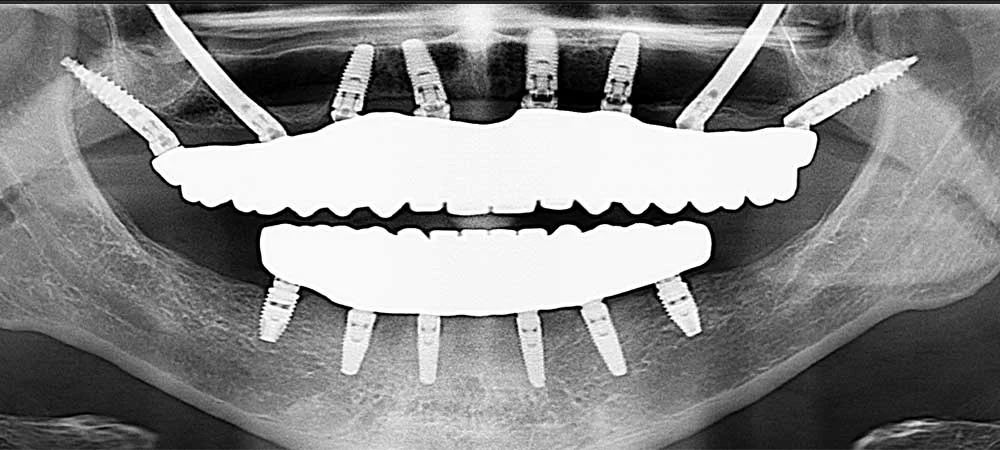

In many full-arch and posterior maxillary cases, conventional implants struggle due to lack of bone support, sinus pneumatization, or difficulties in grafting. Pterygoid implants offer a powerful solution by anchoring into the dense pterygoid apophysis (a complex of the maxillary tuberosity, palatine bone, and pterygoid process) to deliver excellent posterior support and eliminate distal cantilever zones. As reported in a 2022 study co-authored by Dr. Vivek Gaur, pterygoid implants engage the apophyseal bone and reduce dependency on the tuberosity itself, thereby enhancing stability in challenging anatomical situations.

- Cross-Arch Stability: When splinted with anterior implants across the arch, pterygoid implants enhance the rigidity and longevity of full-mouth prostheses, even in compromised bone cases.

Because of these advantages, pterygoid implants are regarded as a strategic tool in advanced implantology – especially in full-mouth restorations where posterior support is critical. These are also suitable for single-tooth implants, especially where traditional implants fail.